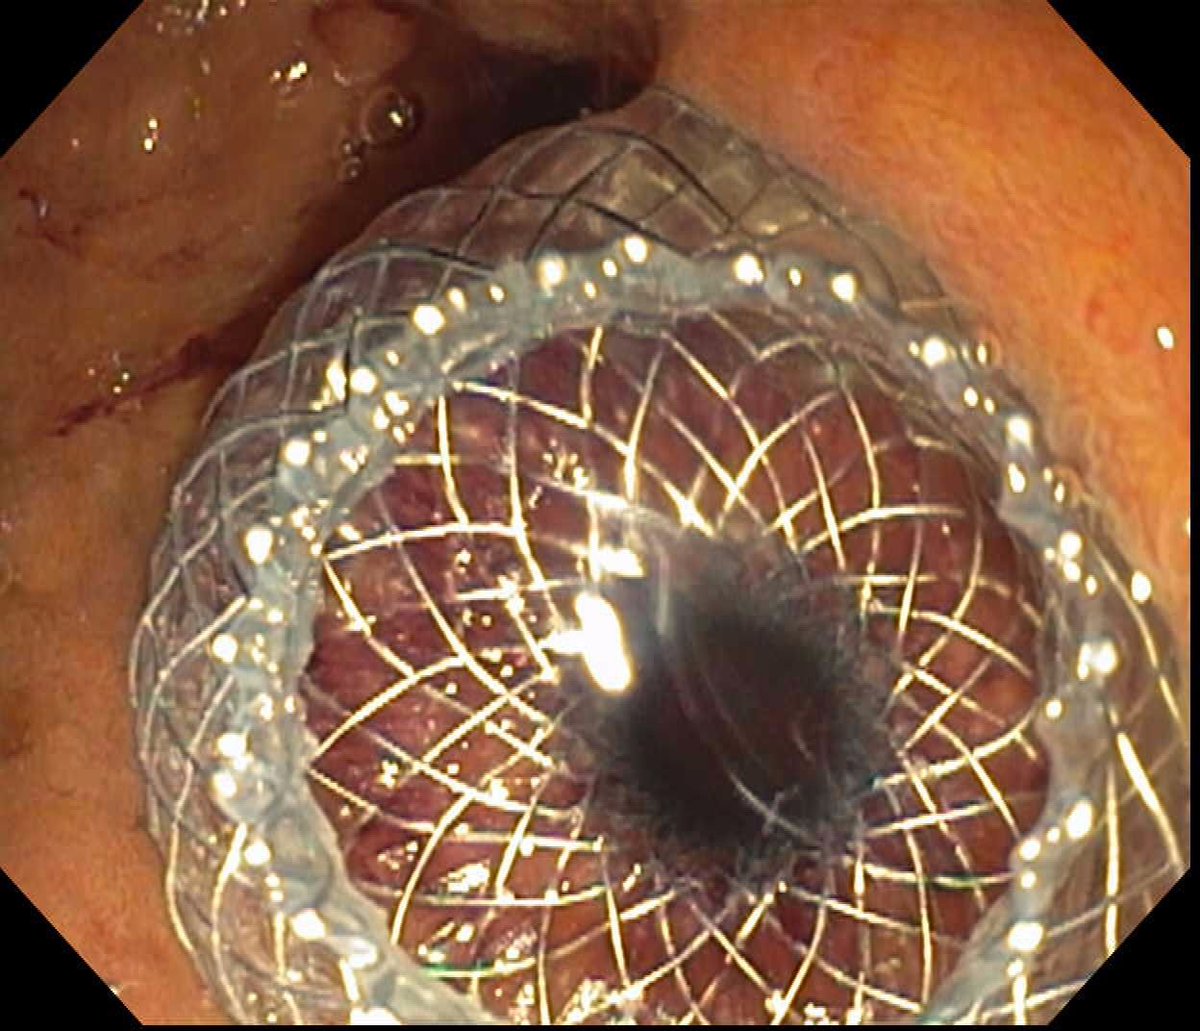

Two is better than one. Our (Tarun Rustagi Sergio A. Sánchez-Luna, MD, DABOM (He/Him/His)) study using dual transpapillary gallbladder stents in acute cholecystitis showing long term recurrence rate of 4.76% and adverse event rate of 9.52% during a mean follow-up of 471.74 days. pubmed.ncbi.nlm.nih.gov/34053214/

Two is better than one. Our (<a href="/TarunRustaGI_MD/">Tarun Rustagi</a> <a href="/SanchezLunaMD/">Sergio A. Sánchez-Luna, MD, DABOM (He/Him/His)</a>) study using dual transpapillary gallbladder stents in acute cholecystitis showing long term recurrence rate of 4.76% and adverse event rate of 9.52% during a mean follow-up of 471.74 days.

pubmed.ncbi.nlm.nih.gov/34053214/